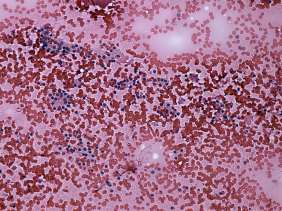

Cytology was performed from one of the moderately hypoechogenic lesions. It was located next lateral to the echonormal lesion. There were two cell populations on the smear: beside regular thyrocytes, follicular cells presenting oxyphilic metaplasia were also found on the smear.

Combined cytological-clinical-sonographic diagnosis: benign lesion presenting oxyphilic metaplasia.